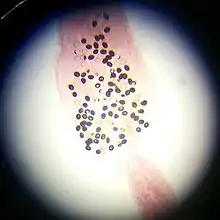

К известным биогельминтам относится бычий цепень — возбудитель опасного заболевания тениаринхоз. Также встречаются свиной цепень, вызывающий тениоз и цистицеркоз; трихинелла, являющаяся причиной трихинеллеза.

К группе биогельметинов относятся плоские и круглые черви, такие как трематод, цестод, нематод[2].